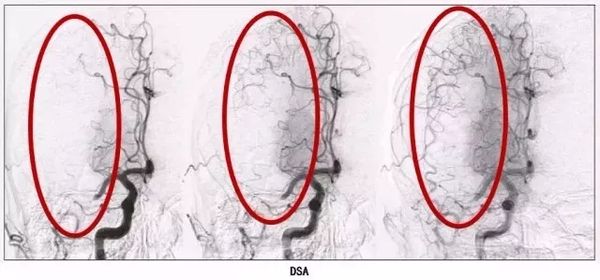

我们可以看到前面提到的这位患者的血管造影。一开始血管发生了堵塞,由于堵塞,最左侧的造影图里,红色圈中几乎没有血液通过,经过慢慢的恢复,侧支循环一点点建立,血液能够正常通过了!